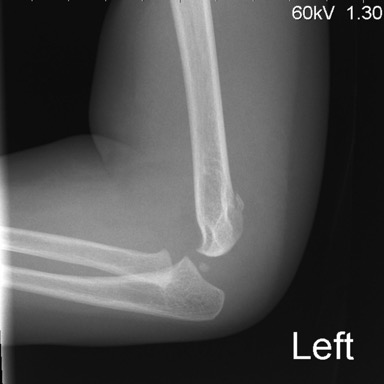

- Posterior fat pad of the elbow lies deep within the olecranon fossa while the anterior fat pad is not flanked by bone on either side (see figure below). Hence, on a lateral radiograph, the anterior fat pad should be normally visible and the posterior fat pad should not be visible (see figure below).

- If there is an elbow effusion, it pushes both the fat pads outside, so that the posterior fat pad is no longer masked by the supracondylar ridges and becomes visible on the radiograph. The anterior fat pad which was normally seen adjacent to the humerus, gets lifted up inferiorly and a fluid fat interface can be seen (sail sign).

- Do note that if the elbow effusion is very large, both the anterior and the posterior fat pads may get completely effaced and not visible (false negative). However, you should be able to see significant soft tissue swelling in such cases and make the diagnosis (figure below).